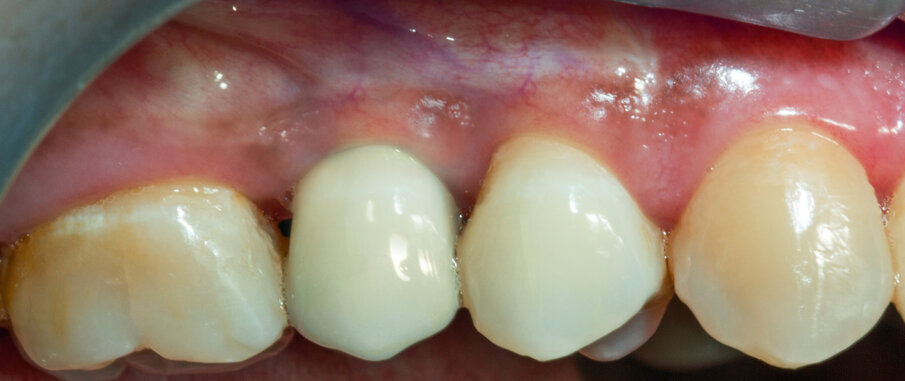

Viene inserito nel centro della cresta neoformata un impianto osteointegrato Neoss Tapered 4.0 x 13 mm con torque di inserimento di 60 Ncm e ISQ 80 (Figg. 22-24). La rigenerazione ossea crestale permette di inserire l’impianto in una posizione protesicamente guidata e con 2 mm di tessuto osseo vestibolare; questa situazione migliora la prevedibilità della riabilitazione implanto-protesica29-33. Dopo 2 mesi di provvisorizzazione si cementa il manufatto protesico definitivo (Figg. 25-28). Il controllo clinico e radiologico a 6 anni (Figg. 29, 30) mostra la stabilità dei tessuti molli e dell’osso perimplantare. Il confronto tra baseline e 6 anni dalla riabilitazione protesica evidenzia la stabilità nel tempo della rigenerazione volumetrica crestale (Fig. 31).

Fig. 27 - Corona protesica definitiva cementata.

Fig. 29 - Controllo clinico a 6 anni.

Fig. 30 - Controllo radiografico a 6 anni.

Fig. 31 - Confronto tra baseline e 6 anni da riabilitazione implanto protesica.